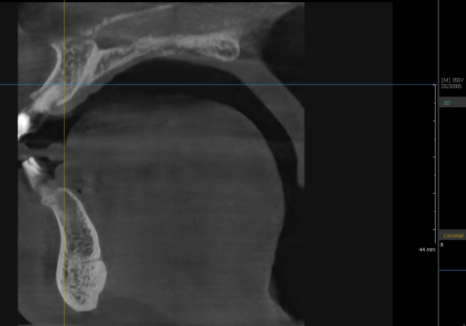

다행히 CT 분석 결과,

잇몸뼈의 폭과 길이가 충분하셔서

발치 당일 즉시 임플란트를

식립할 수 있었습니다.

240119